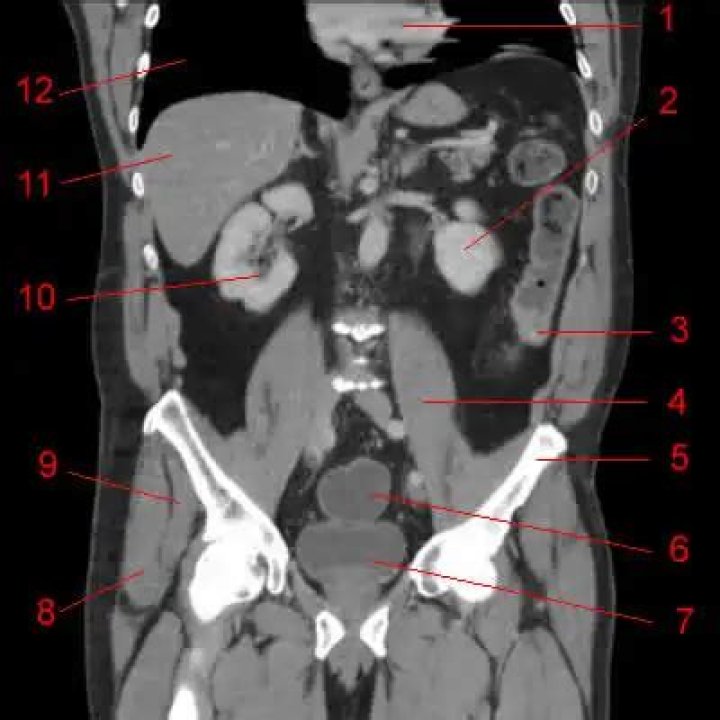

I do not own copy right to this image. Reference: DeMaio, D. N. (2018). Chapter 4. In Mosby's exam review for Computed Tomography (p. 66). essay, Mosby.